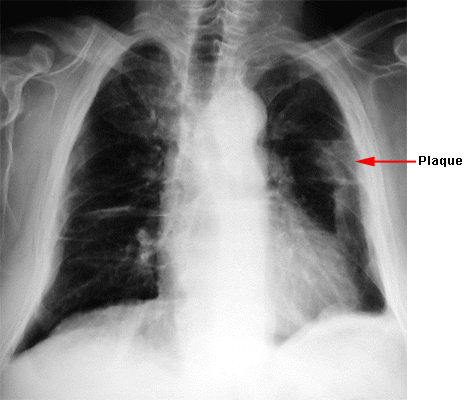

Affections consécutives à l’inhalation de poussières d’amiante : épidémiologie, étiologie, diagnostic, prévention, réparation – UVMT